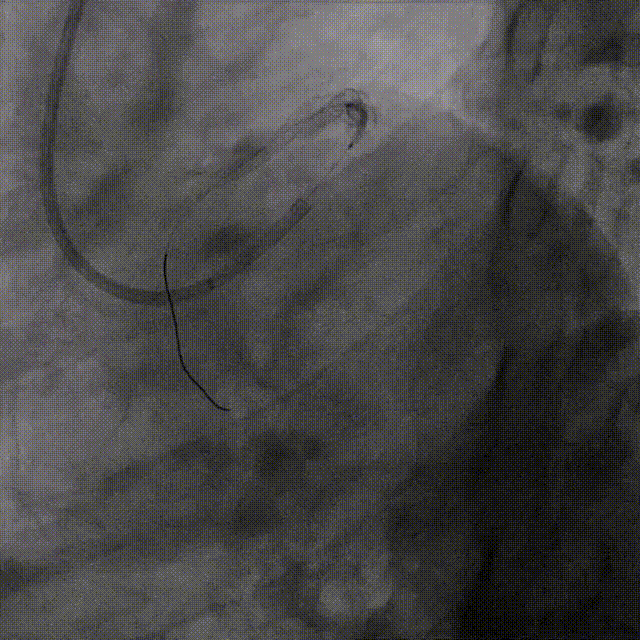

导丝通过闭塞段

在IVUS辅助下,顺利找到LAD开口方向

将HighTrack 1.5Fr 微导管送至LAD闭塞段开口处加强支撑,使用导丝升级技术,先后送入BMW、XT-R、P150、GAIA2导丝通过闭塞段远端